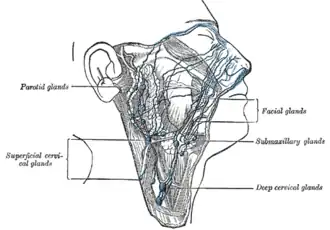

Additional images

-

The lymphatics of the face.

The lymphatics of the face.